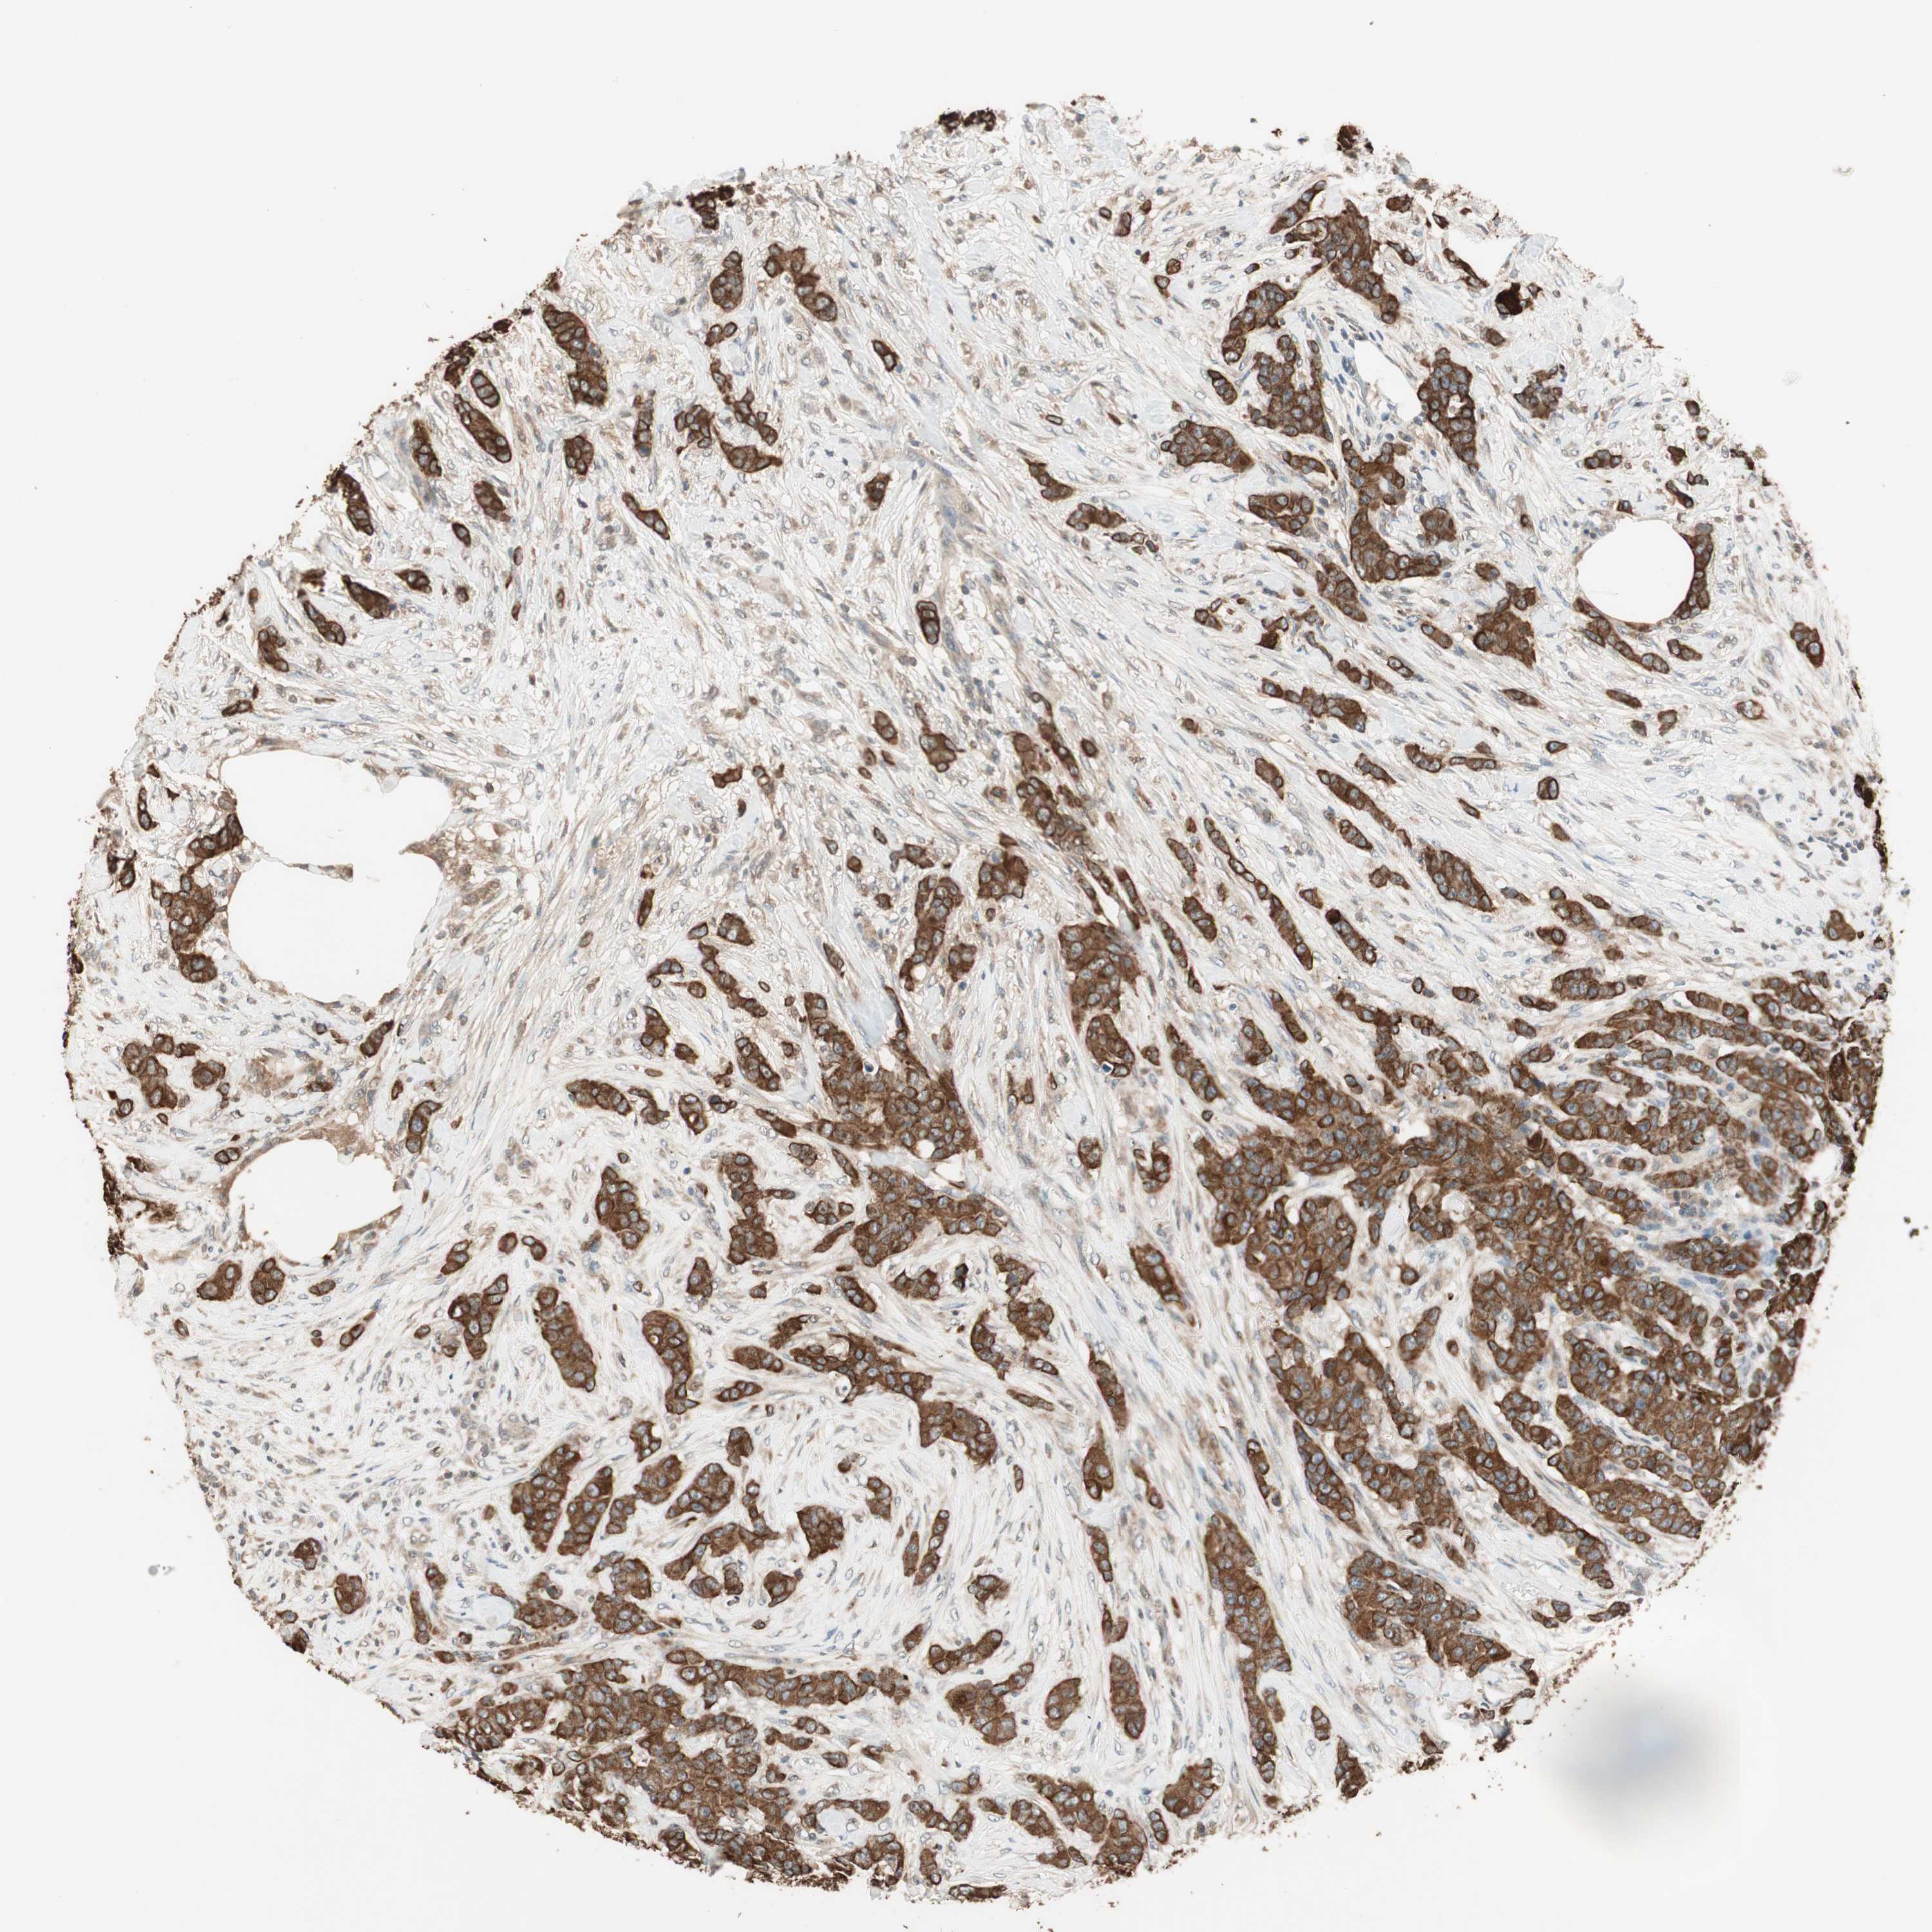

BRCA TCGA BRCA VALIDATION PROTEIN EXPRESSION

ANTIBODIES

AND

VALIDATION